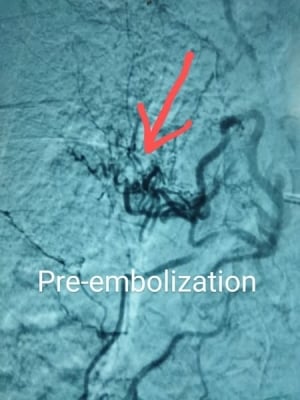

وقد أُجريت عملية انصمام الشريان القصبي (Bronchial Artery Embolization) بنجاح في غرفة القسطرة، تحت قيادة مباشرة من الدكتور محمد نصر نزال، أخصائي الأشعة التداخلية والقسطرة، الذي أظهر براعة استثنائية في إدارة الحالة والتدخل الدقيق لإنهاء النزيف الرئوي عبر القسطرة الفخذية، مستخدمًا جزيئات دقيقة (PVA particles) لإغلاق الشريان النازف. لقد شكّل هذا التدخل لحظة حاسمة أنقذت حياة المريض دون الحاجة لأي تدخل جراحي، وبلا مضاعفات تُذكر. وشاركه في الإجراء الدكتور أنس شهاب، أخصائي الأشعة التداخلية والقسطرة.